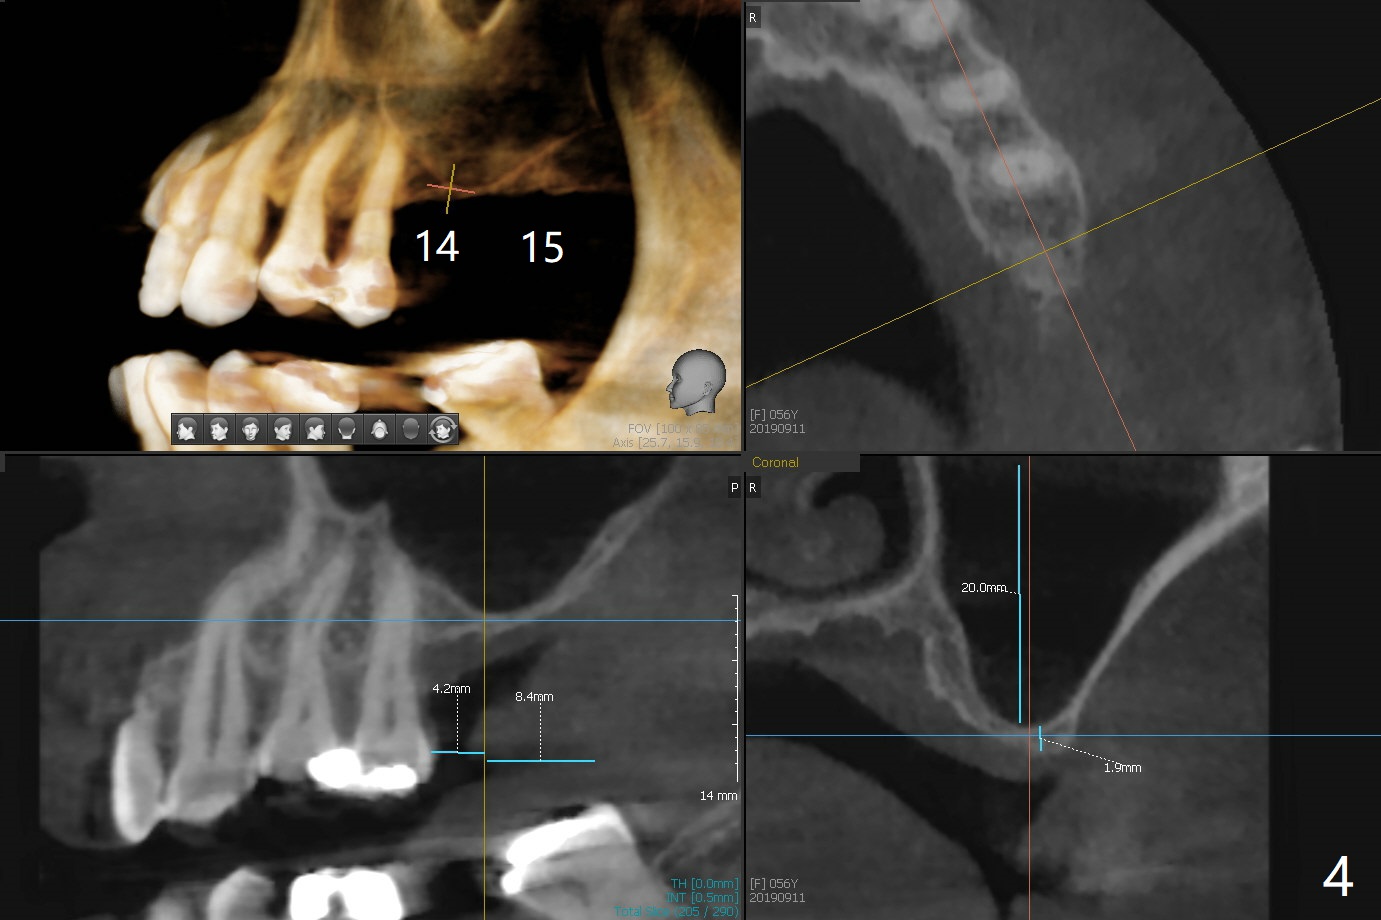

A 56-year-old woman without much posterior support has fractured #7-9 FPD (Fig.1). Since the bone at #7 is thinner buccopalatal than that of #9 (compare Fig.2,3), a shorter implant will be placed at #7 with an angled abutment. External sinus lift is required with PRFx2 before implantation at #14 and 15 (Fig.4). For #19 with the narrow mesiodistal space, a narrow implant is indicated (Fig.5).